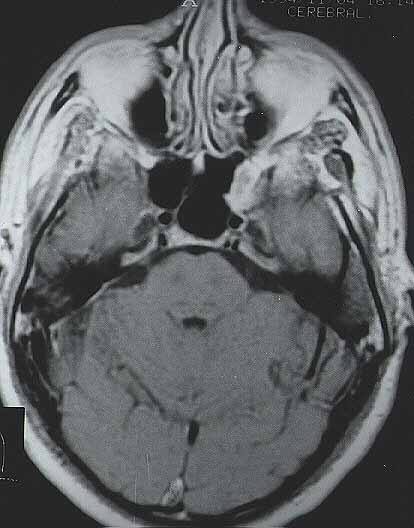

fig. 11

Fig. 11. Imagen axial de MRI con contraste ponderada en T1 tomada tras la cirugía, en la que se observa la ausencia de lesión residual.